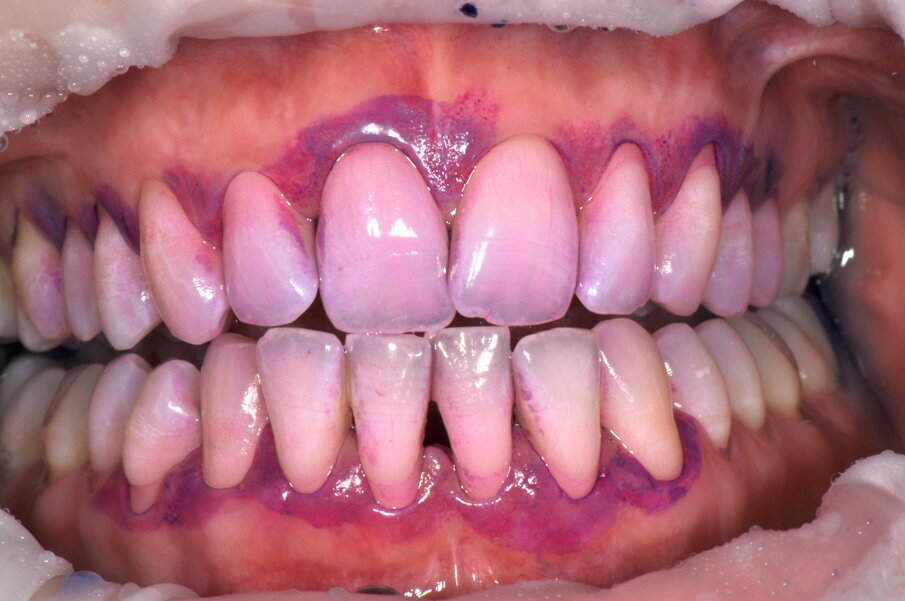

- Applicazione del rilevatore di placca bifasico: permette la distinzione fra i depositi di placca recenti da quelli meno recenti ( 1a-1c);

Figg. 1a-1c - Applicazione del rilevatore di placca che verrà usato come guida durante la terapia, nel versante vestibolare (1a), palatale (1b) e linguale (1c). Si noti lo scarso livello di igiene orale domiciliare e l’assenza di utilizzo dei presidi interdentali.